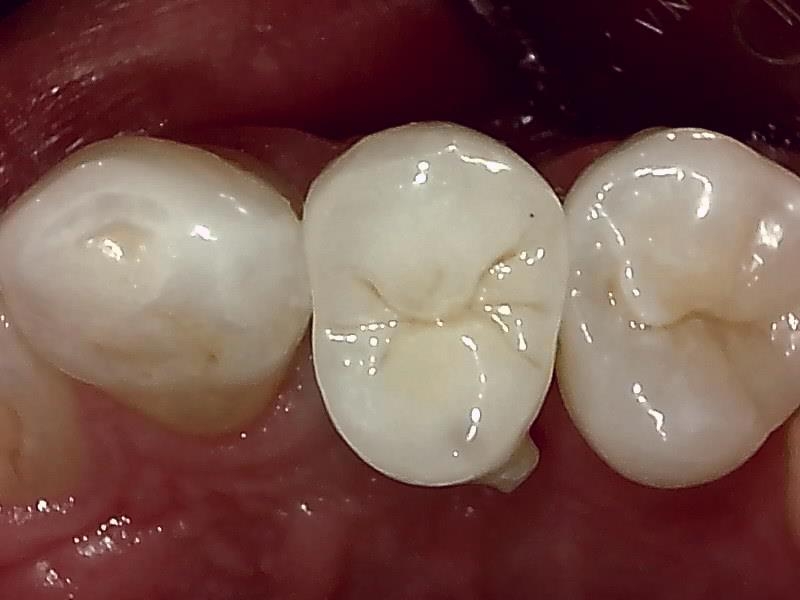

インプラントの上部構造 (左上)

(ジルコニアセラミッククラウン)